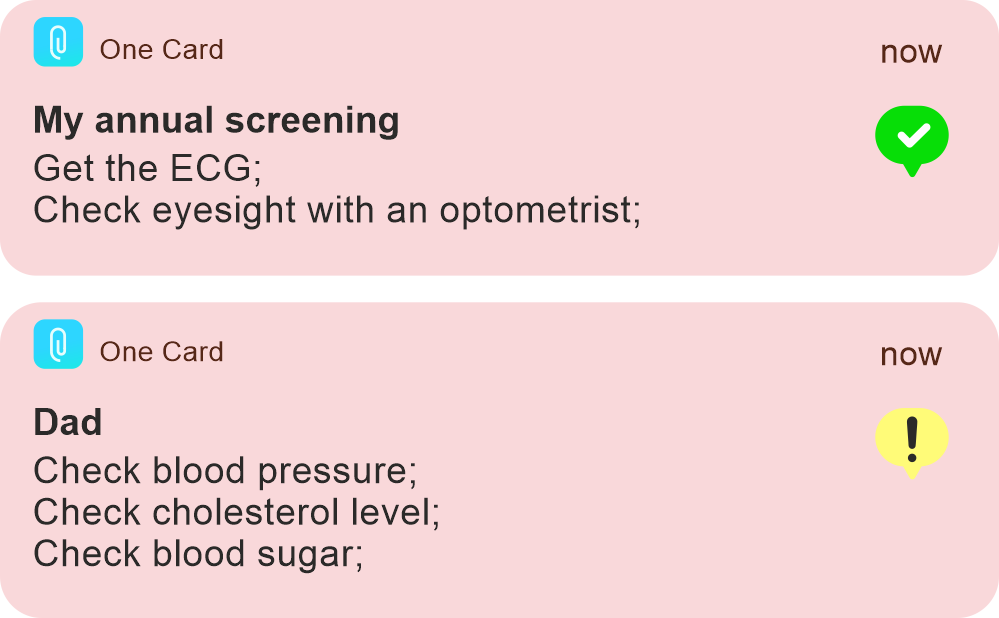

Care mode

for the oldest

family members

for the oldest

family members